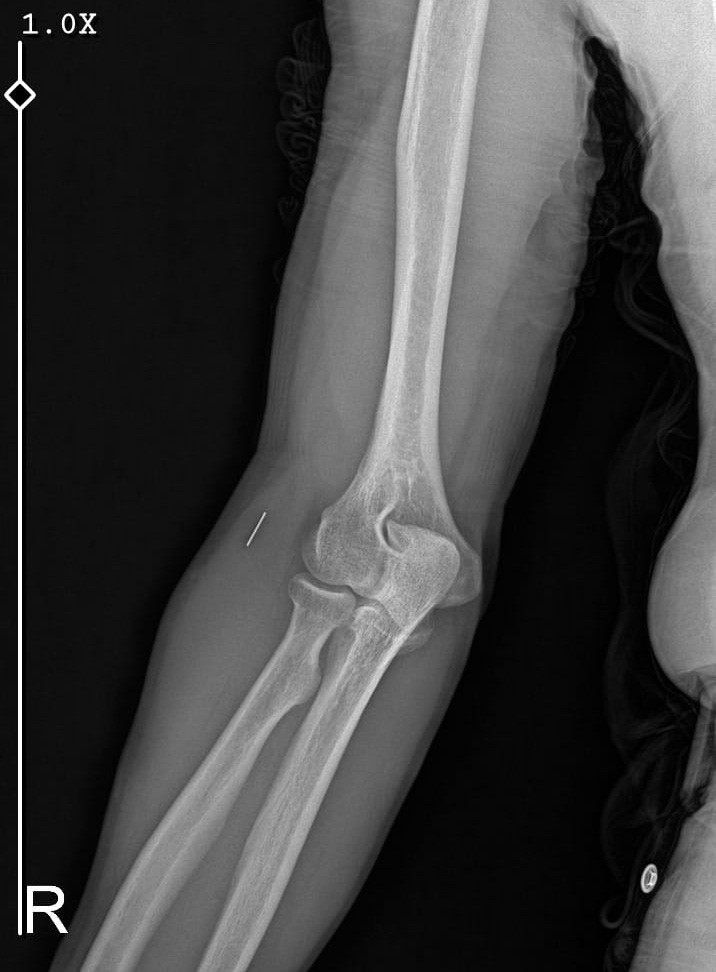

Edinilen bilgiye göre, 7 Haziran 2025'te Kurban Bayramı dolayısıyla bıçak temizlerken sağ el başparmağını kesen Nurettin Güleryüz (34), bir özel hastanenin acil servisine başvurdu. İddiaya göre, hastanede detaylı tetkik yapılmadan pansuman uygulanan Güleryüz'e ilaç reçete edilerek taburcu edildi. Şikayetlerinin devam etmesi ve kanamanın durmaması üzerine ertesi gün aynı hastaneye tekrar giden Güleryüz'e bu kez dikiş atıldı. Parmağını hareket ettirememesi üzerine 19 Haziran'da Gebze'deki başka bir özel hastaneye başvuran Güleryüz, tendon yaralanması şüphesiyle tedaviye alındı. Farklı tarihlerde yapılan EMG ve MR tetkiklerinde sinir hasarı ile tendon kopması tespit edilen hasta, 2 Eylül'de ameliyat edildi. Süreç içerisinde parmağın çürüdüğü ve kurtarılamayacağının belirtilmesi üzerine Güleryüz, başvurduğu başka bir hastanede ampute operasyonu geçirdi. Öte yandan, ameliyatların ardından ağrıları devam eden Güleryüz'ün kolunda metal parça bulunduğu ve bu parçanın parmak bölgesinden dirseğe doğru ilerlediği öne sürüldü. Ayrıca, fabrikada temizlik personeli olarak çalışan Nurettin Güleryüz'ün hastane sürecinde işten çıkarıldığı da öğrenildi.

İkinci hastanedeki ameliyatların ardından kolunda ağrılar hissettiğini söyleyen Güleryüz, sözlerini şöyle noktaladı: "Doktorlara bileğime doğru ağrılarım olduğunu sürekli ifade etmeme rağmen beni dinlemediler. Sonradan kolumda metal kaldığını öğrendik. Bunun ihmal olduğunu düşünüyoruz. Çünkü kola metal nasıl girebilir? Ben 9 aydır çalışamıyorum. Kalp rahatsızlığım sebebiyle yüzde 46 engelliyken şu anda yüzde 75 engelli durumuna düştüm. Erken emeklilik dilekçesi verdim ancak henüz sonuç gelmedi. Bu konuda çok mağdurum. Yetkililerin bunu duymasını istiyorum. Savcılığa suç duyurusunda bulunduk. Yaklaşık 9 aydır henüz soruşturma izni gelmedi. Süreci bekliyoruz, henüz dava açılmış değil. Kolumda bırakılan metal ilerliyor. Pazartesi günü bunun için de operasyon geçireceğim. Çıkarılıp çıkarılamayacağı net değil. Elimde titremelerim var, çalışamıyorum ve işveren tarafından işten çıkarıldım. Yetkililerden destek ve konunun incelenmesini talep ediyorum."